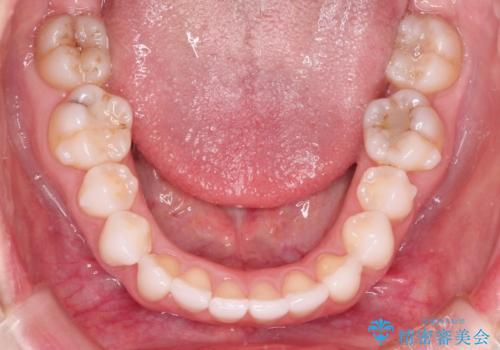

八重歯をマウスピース矯正で治療し、レーザーホワイトニングを行った症例

- 主訴:「右上犬歯を引っ込めて、歯並びをキレイにしたい」

右上の八重歯を気にされてご来院されました。結婚式を控えていたため挙式にまでに可能な限りキレイにしたいとのことでした。

右上の犬歯の歯茎は矯正前から退縮を起こしていましたが、矯正後もその退縮に関しては変化がありませんでした。今回は患者様が歯肉退縮に関しては治療をご希望ではありませんでしたが、当院ではこのように歯茎が下がり露出した根面を、歯茎を移植することでカバーし見た目を改善する手術を行っています。